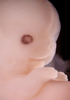

Carnegie Stage 20 (50 post-ovulatory days)

Most embryos at stage 20 are approximately 50-51 postovulatory days old and measure 21-23 mm in length. Distinguishing criteria for this stage include upper limbs slightly bent at the elbows, short stubby fingers, hands curving over the cardiac region but still far apart from each other, and a fringe-like vascular plexus that marks growth centers laterally in the superficial tissues of the head.

Although some of the photographs below show abnormal embryos, the animations and MRI slice images all depict normal embryos. Abnormal embryos are noted in the titles of the large photos when they are opened.